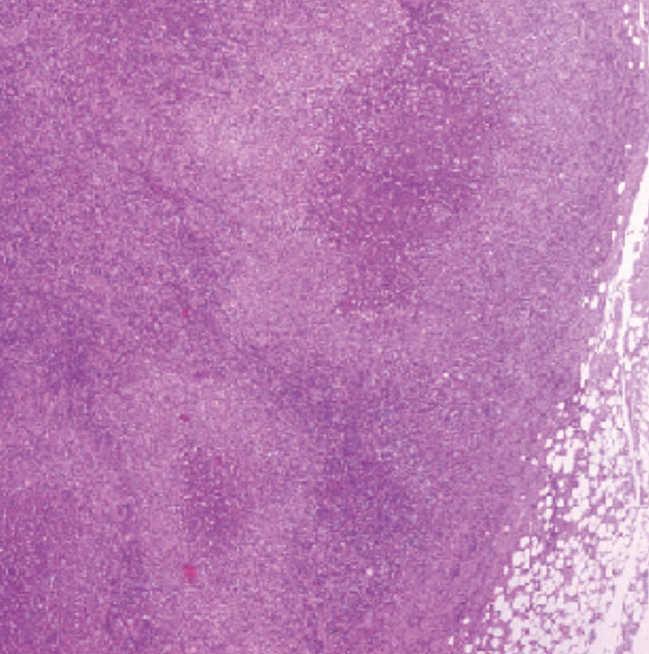

She was observed on admission by an otorhinolaryngologist who prescribed metronidazole plus amoxicillin and clavulanate for a nasopharynx´s infection. Serologies for Epstein-Barr virus, herpes virus, cytomegalovirus, toxoplasmosis, brucella, leishmania, and HIV infection were negative. Blood culture was sterile. Chest and abdominal CT scan without changes. Quantiferon test for tuberculosis was indeterminate. Peripheral blood cytometry and cytometry of ganglion did not showed immunophenotypic alterations compatible with lymphoma. An ganglion biopsy was performed and histological examination revealed reactive lymphadenitis with central necrosis (Ziehl neelsen was negative) alterations compatible with CSD (Figure 1 and Figure 2). She stopped the initial antibiotherapy on the 6th of internment (without improvement of complains) and began azithromycin 500mg on day one, followed by 250mg for four days. There has been a good clinic improvement with involution of ganglion swelling and resolution of the pain and fever. One month later the patient was asymptomatic, without any signs of recurrence.

Figure 1. Ganglion biopsy Focus of necrosis, some surrounded by granulomatous inflammation in cortical region (H&E, original magnification x40).